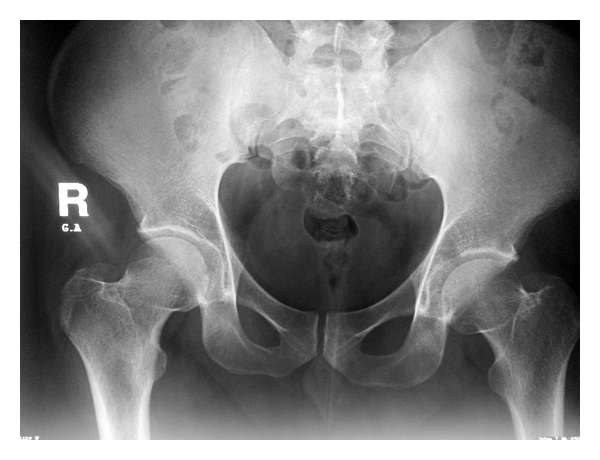

A 29-year-old male presented with a 12-month history of left groin pain. Pain exacerbates at night and was relieved with nonsteroidal anti-inflammatory drugs. On physical examination, pain was felt during maximal flexion and extension of the left hip. Anteroposterior pelvic radiograph showed a suspicious round lesion at the junction of the weight-bearing area of the acetabulum with the notch (Figure 5). Computed tomography showed a 0.9 cm sized sclerotic bony lesion within a circular lucency in the superior portion of the acetabulum (Figure 6). The radiographic diagnosis was osteoid osteoma.